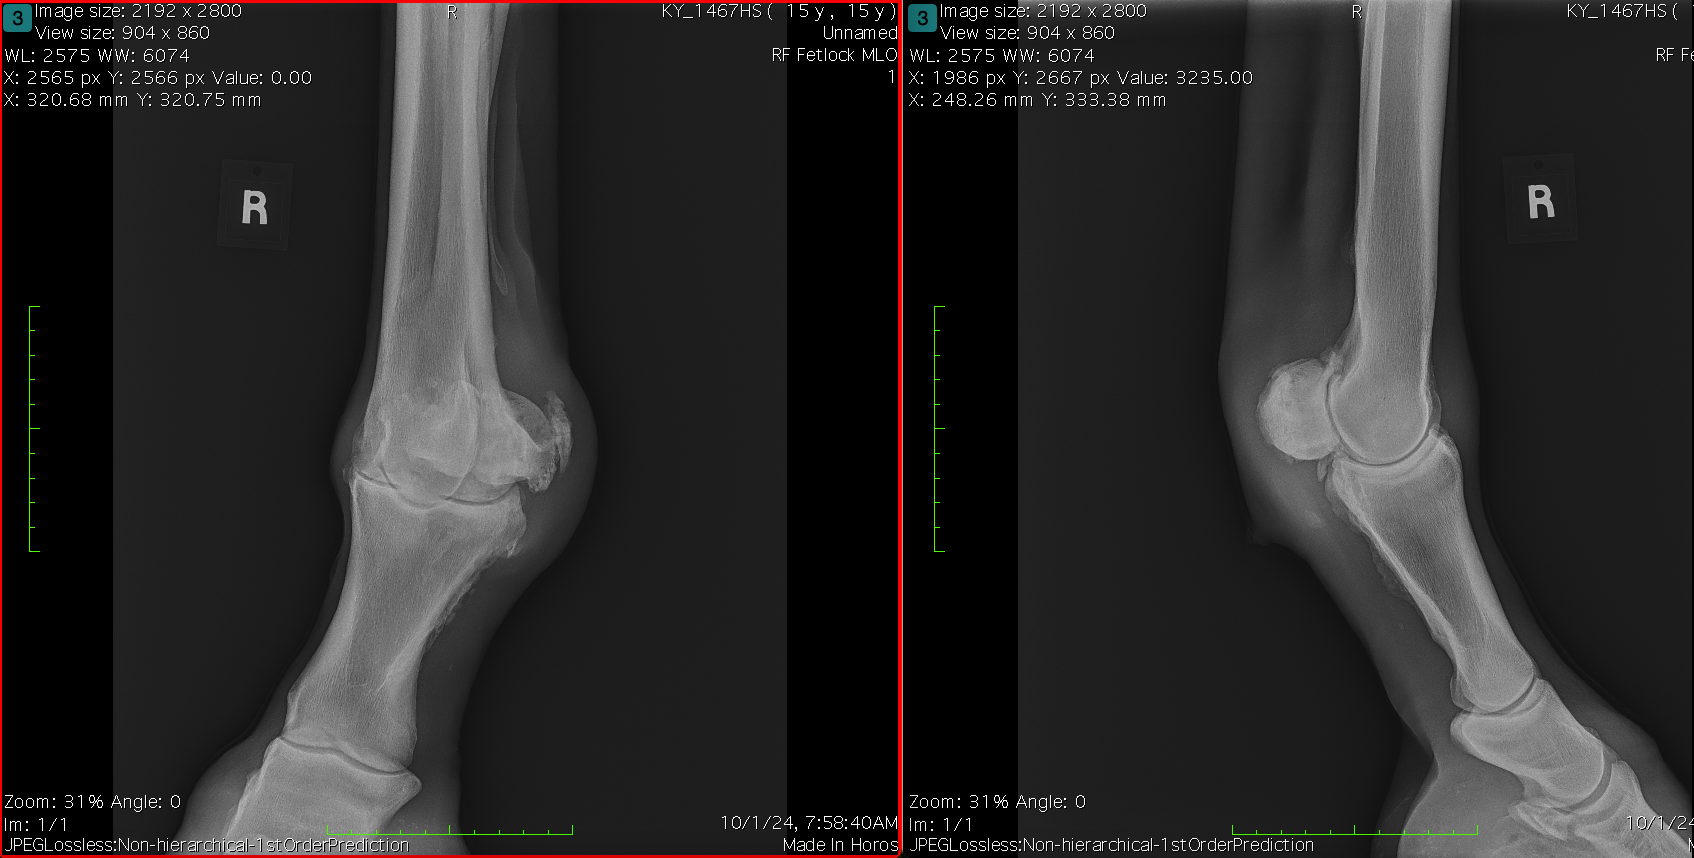

Diagnosis and Procedure: Degenerative arthritis of the fetlock joint, pain leading to overloading the other foot. Fetlock arthrodesis was performed.

Treatment:

Amikacin 250 mg/ml

Daily dose administered: 6 ml

Days of treatment: 5 days

Conclusion: Vetlen Pouch worked well. The surgeon liked the ability to instill the antibiotics onto the plate for 5-days post-op. The mare has done well and is back home.